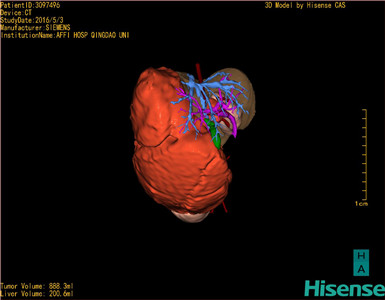

将0.625mm双源薄层CT资料的静脉期和动脉期Dicom格式文件导入海信CAS系统。

通过调节窗宽窗位调整CT序号,对肿瘤,肝实质,胆囊,下腔静脉,肿瘤,肝动脉、门静脉及肝静脉等进行三维重建;系统自动计算肿瘤体积和肝脏体积。(模拟手术操作,自动计算切除肿瘤体积。

麻醉成功后,患儿取平卧位,右腰下垫枕,2.5%碘伏消毒手术区皮肤,铺无菌巾单。取右上中腹纵切口长约10cm,切开皮肤、皮下组织、肌层和腹膜。探查见肿瘤呈囊实性,约1/3为脂肪成分,整个肿瘤大小约20*18*10cm,充满整个腹腔,包膜完整,与周围组织分界清楚,用吸引器抽吸囊内液体减压,见囊内液体清亮,见肿瘤与下腔静脉,右肾静脉,右肾动脉联系紧密,现游离下腔静脉,右肾动脉,右肾动脉,结扎肿瘤营养血管后,将肿瘤完成切除。腹膜后放置引流管一根。检查无活动性出血,清点纱布器械无误,依次缝合腹壁各层。手术顺利,麻醉满意,出血不多,未输血,术后病人先进入麻醉恢复室,苏醒后回病房。术后标本送病理检查。手术时手术者可开启Hisense CAS系统手势控制功能,对肿瘤的解剖结构进行实时、全方观察、评估,起到术中导航作用。

术前三维重建:

重建图片